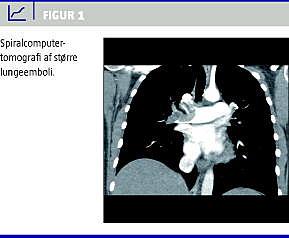

I løbet af få timer blev hendes tilstand forværret, og hun havde et besvimelsestilfælde. Hun havde nu sinustakykardi på 120, saturation 96% med 4 l ilt på næsekateter. Gentaget ekkokardiografi viste dilaterede højresidige kamre og forhøjet tryk over trikuspidalklappen. Obstetrisk set fandt man et levende foster i hovedstilling med normal tilvækst og normal kardiotokografi (CTG). Patientens kliniske tilstand blev forværret over de næste timer, og man overvejede trombolysebehandling. Mhp. sikker diagnose foretog man spiralcomputertomografi (spiral-CT), som bekræftede større embolier bilateralt i arteria pulmonalis samt de nedre segment arterier (Figur 1 ).